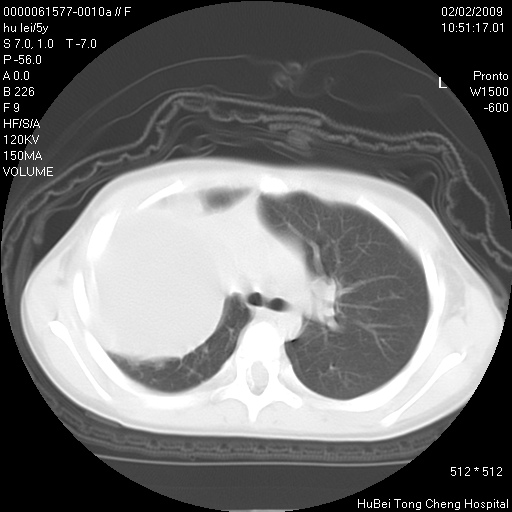

标题: PED1732:M5Y,右肺囊性占位!

患者:男,5。无明显不适,拍胸片考虑右肺囊肿。

行ct扫描,图象如下: